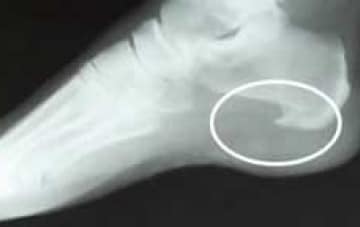

Heel spurs often form when the tension in the plantar fascia starts to pull the outer layer of the bone (the periosteum) away from its attachment to the heel bone.

To protect and reinforce this now weakened and vulnerable area the body starts to lay down calcium and a heel spur slowly forms over a period of time.